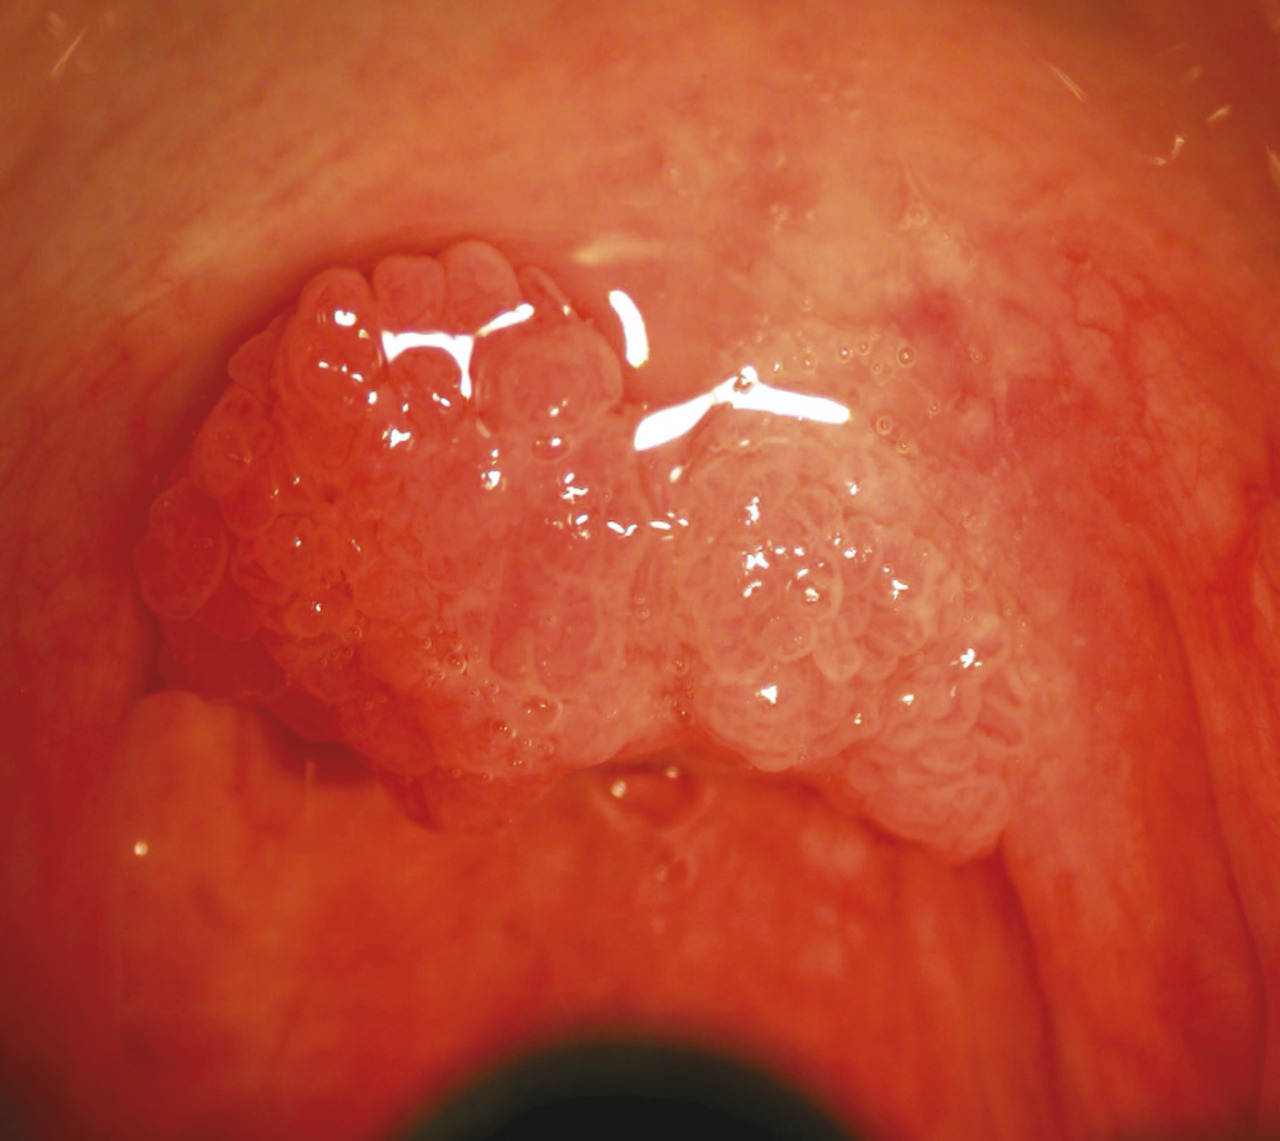

L’examen clinique de la cavité buccale dépiste des lésions précancéreuses telles que l’érythroplasie (fig. 5) ou la leucoplasie (fig. 6). Il recherche également la présence de lésions papillomateuses (fig. 7) évocatrices d’infection à HPV. Les lésions ulcérantes ou bourgeonnantes évoquent un cancer invasif (fig. 8) ; souvent douloureuses, elles peuvent s’accompagner d’une dysphagie, voire d’une limitation de l’ouverture buccale (trismus). On recherche une lésion ulcérante ou bourgeonnante de l’amygdale (fig. 9), de la base de la langue, du voile du palais ou de la paroi pharyngée postérieure. Il peut s’agir parfois d’une simple asymétrie.